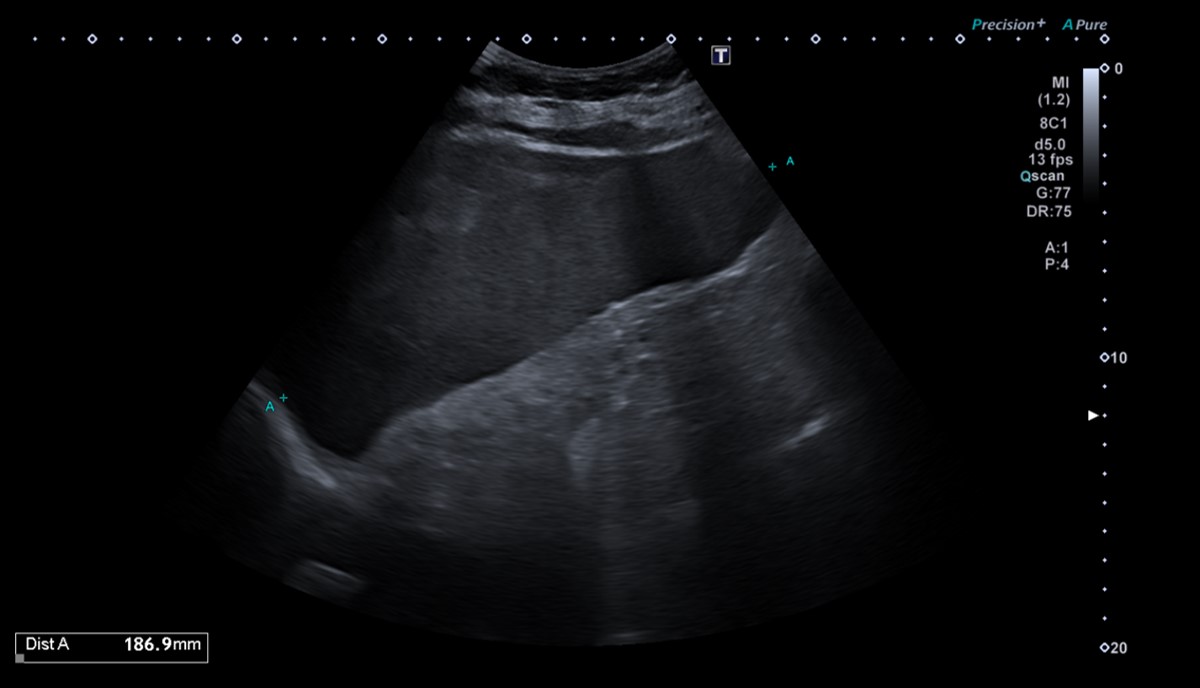

Se realiza ecografía clínica con esplenomegalia de 18 cm con líquido libre en receso esplenorrenal e interasas. Hígado con tamaño y morfología normal con atenuación aumentada de parénquima en probable contexto de hepatopatía difusa. Riñones de tamaño y morfología normal, con buena diferenciación corticomedular. No se observa dilatación de la vía excretora. Vejiga escasamente replecionada sin visualizar engrosamientos focales de la pared.